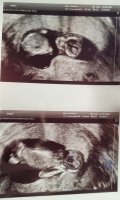

Da har vi vært på ul,og alt ser strålende ut!:D Jeg er så letta!:smug:

Å så ser det (ganske tydelig) ut som det blir en lillebror:joyful:

Kroppen målte til 13+2,akkurat det jeg har går ut fra. Men hodet målte til 13+3,og sønnen jeg har fra før har alltid hatt et stort hode,så det hørtes riktig ut:hilarious::hilarious: